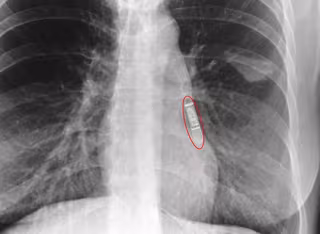

Imagen radiológica tras la implantación.

EP/GOBIERNO DE NAVARRA

La novedad del dispositivo implantado por primera vez en el Complejo Hospitalario de Navarra es su reducido tamaño (más pequeño que el capuchón de un bolígrafo), lo que permite que su implantación pueda hacerse sin utilizar bisturí como hasta ahora, y, por tanto, sin puntos de sutura que deban ser retirados con posterioridad. Así, el 'Holter' se implanta a través de una mínima incisión de tan sólo unos pocos milímetros mediante la inyección del aparato debajo de la piel.